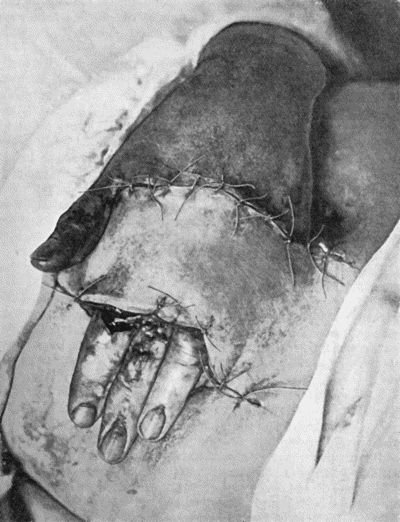

Fig. 1.—Ulcer of back of Hand covered by flap of skin raised from anterior abdominal wall. The lateral edges of the flap are divided after the graft has adhered.

| 1. | Ulcer of Back of Hand grafted from Abdominal Wall | 15 |

Another modification is to raise the flap but leave it connected at both ends like the piers of a bridge; this method is well suited to defects of skin on the dorsum of the fingers, hand and forearm, the bridge of skin is raised from the abdominal wall and the hand is passed beneath it and securely fixed in position; after an interval of 14 to 21 days, when the flap is assured of its blood supply, the piers of the bridge are divided (Fig. 1). With undermining it is usually easy to bring the edges of the gap in the abdominal wall together, even in children; the skin flap on the dorsum of the hand appears rather thick and prominent—almost like the pad of a boxing-glove—for some time, but the restoration of function in the capacity to flex the fingers is gratifying in the extreme.

Fig. 1.—Ulcer of back of Hand covered by flap of skin raised from anterior abdominal wall. The lateral edges of the flap are divided after the graft has adhered.